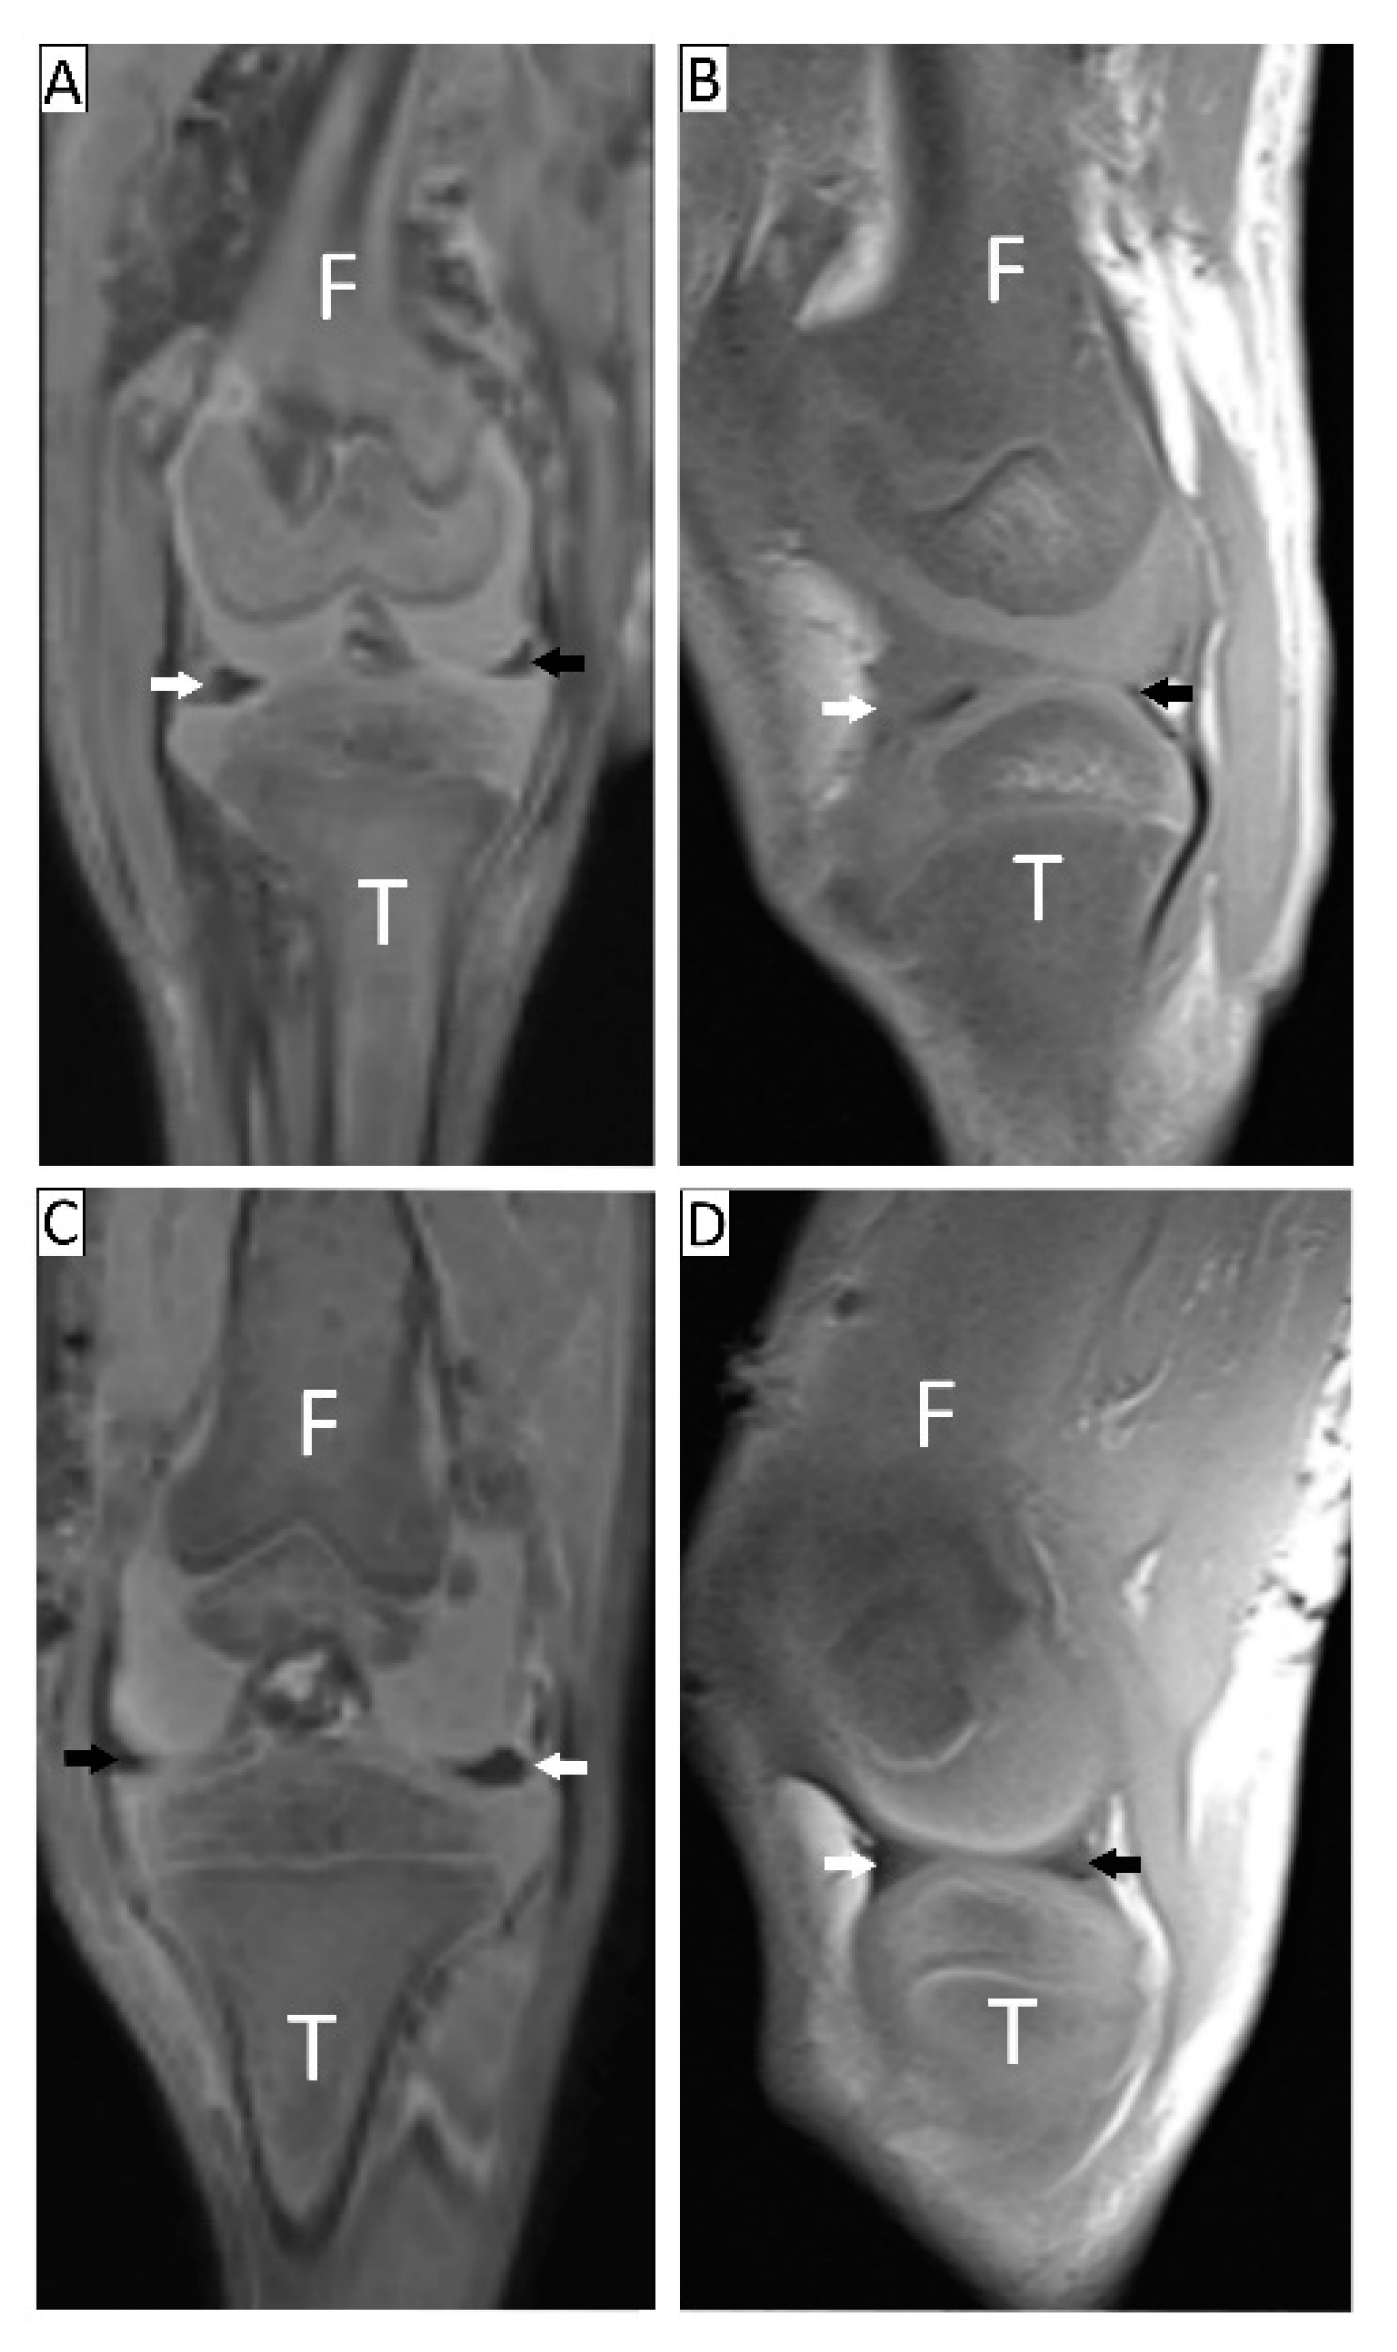

3.1. Radiological and MRI Analyses